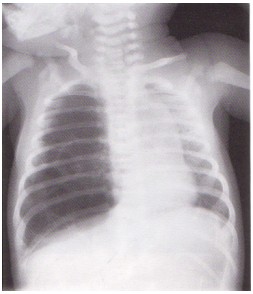

meconium Aspiration syndrome.cmap